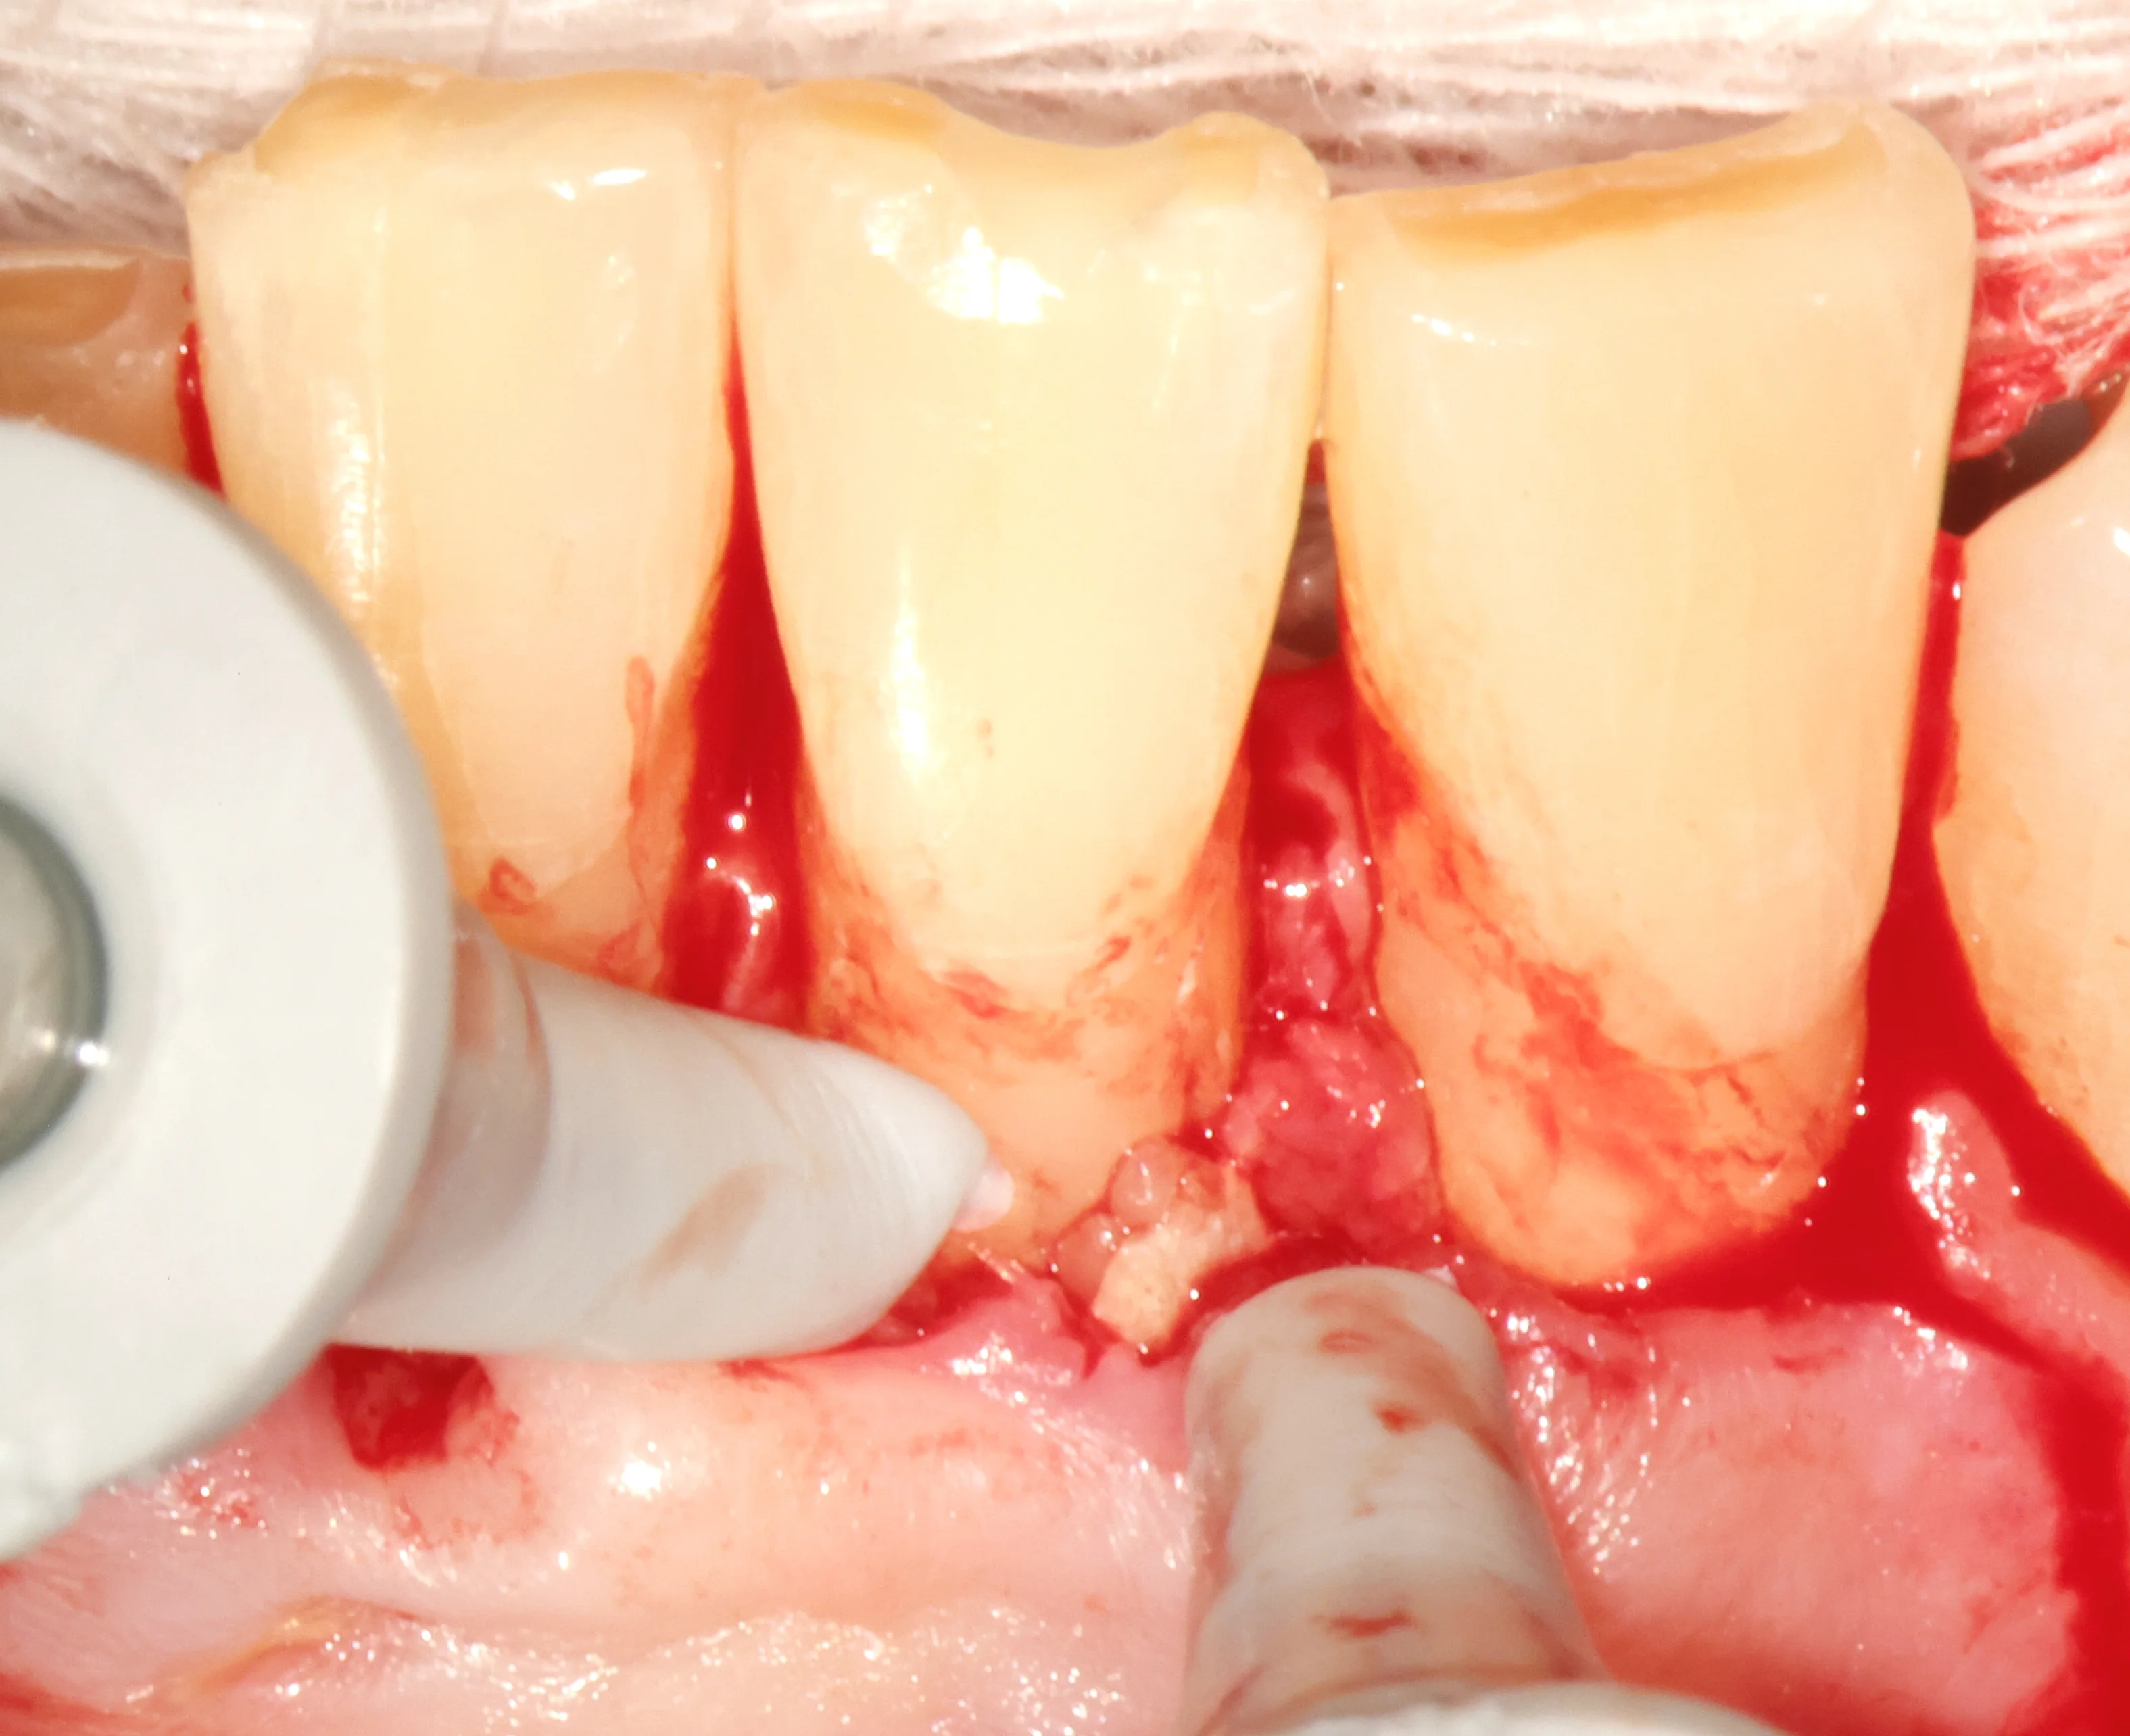

We raised a full-thickness mucoperiosteal flap under local anesthesia to expose the root apices of both teeth. Under 16x microscope magnification, the root surfaces were inspected systematically.

• Key Finding: A vertical cemental tear extending 4-5mm along the root surface of #24, with a loose cementum fragment partially separated from the root.

• Granulation Tissue: Inflammatory tissue had infiltrated the tear defect, creating a pocket of chronic infection invisible on any radiograph.

• Fragment Removal: The loose cementum fragment was elevated and removed with microsurgical curettes under direct visualization.

The original endodontic treatment was technically adequate — the canals were properly cleaned and filled. But a cemental tear is an external root defect. No amount of intra-canal treatment addresses a fracture or tear on the outside of the root surface. This distinction is critical: the problem was structural, not endodontic.

Cemental tears are among the most difficult endodontic diagnoses because they don't appear on conventional periapical radiographs and often present identically to failed root canal treatment. Even CBCT can only suggest the possibility — definitive diagnosis requires direct surgical visualization.